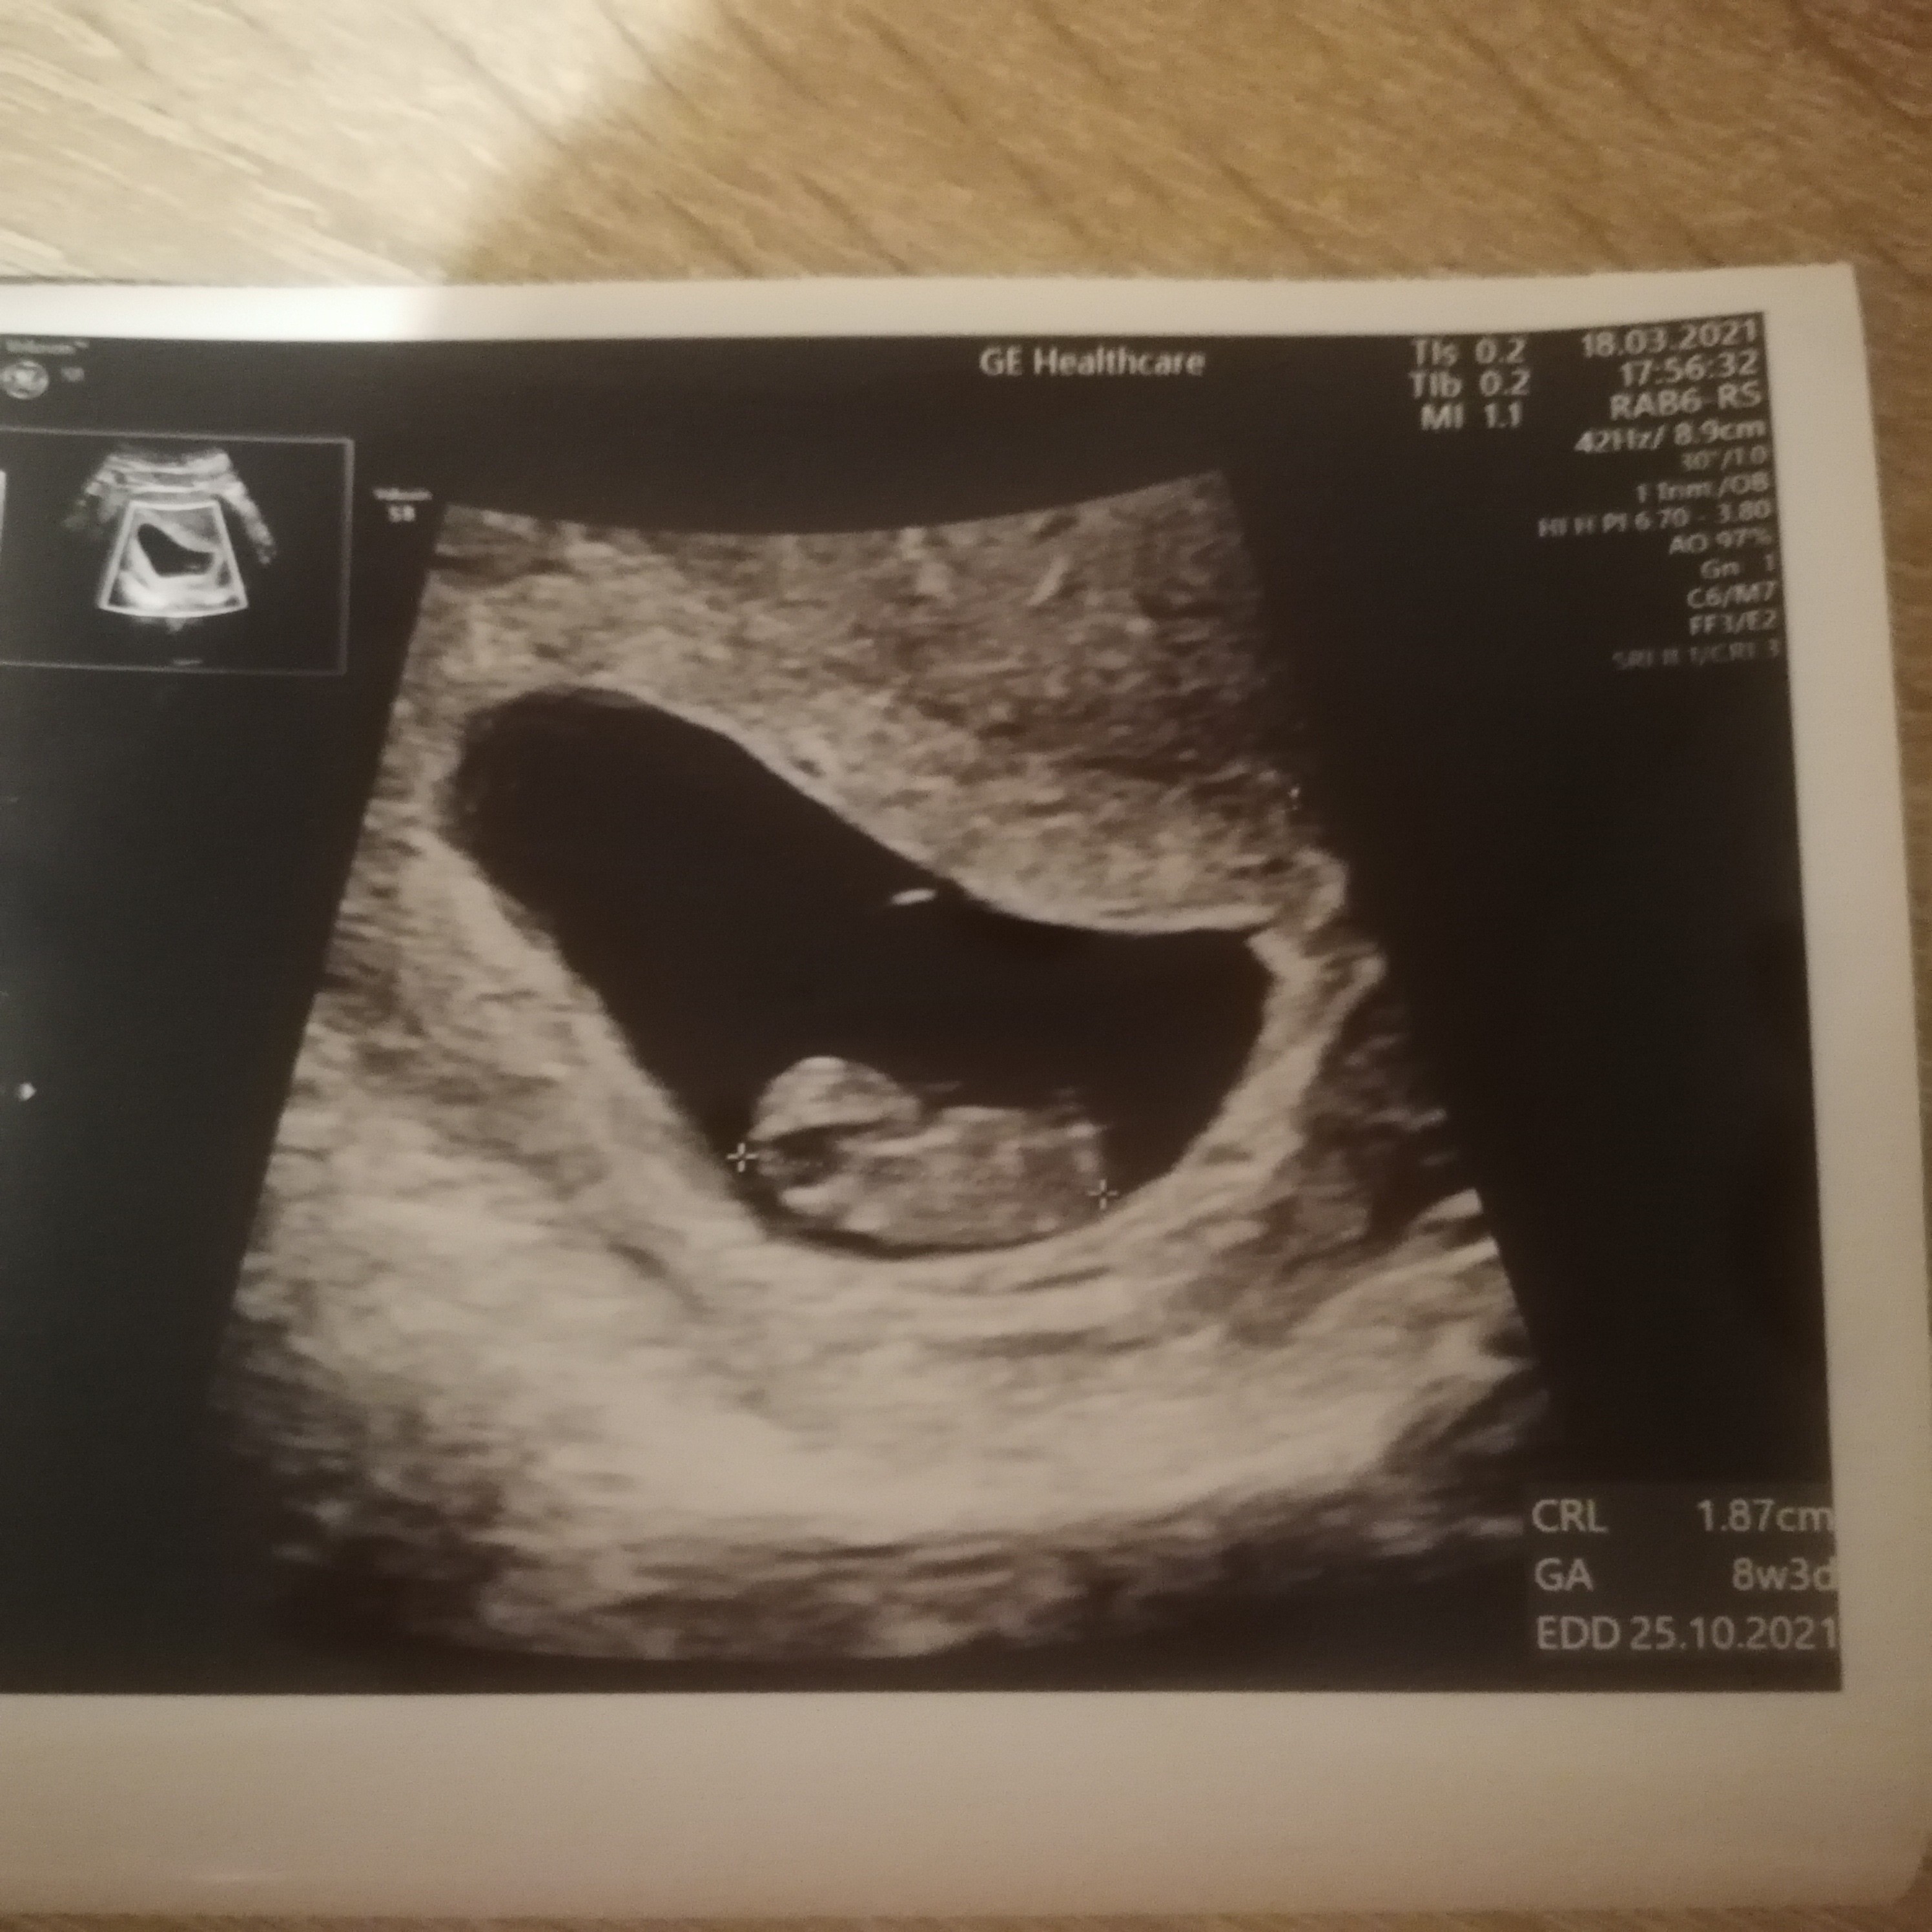

GratulacjeJa już po wizycie rośnie jak na drożdżach albo jak na heparynieserduszko bije pięknie temin już pokazuje na 25.10.

Piękny widok [emoji3059] gratulacje jeszcze raz, niech się zdrowo rozwijaJa już po wizycie rośnie jak na drożdżach albo jak na heparynie [emoji3590][emoji1787] serduszko bije pięknie temin już pokazuje na 25.10. [emoji3590]